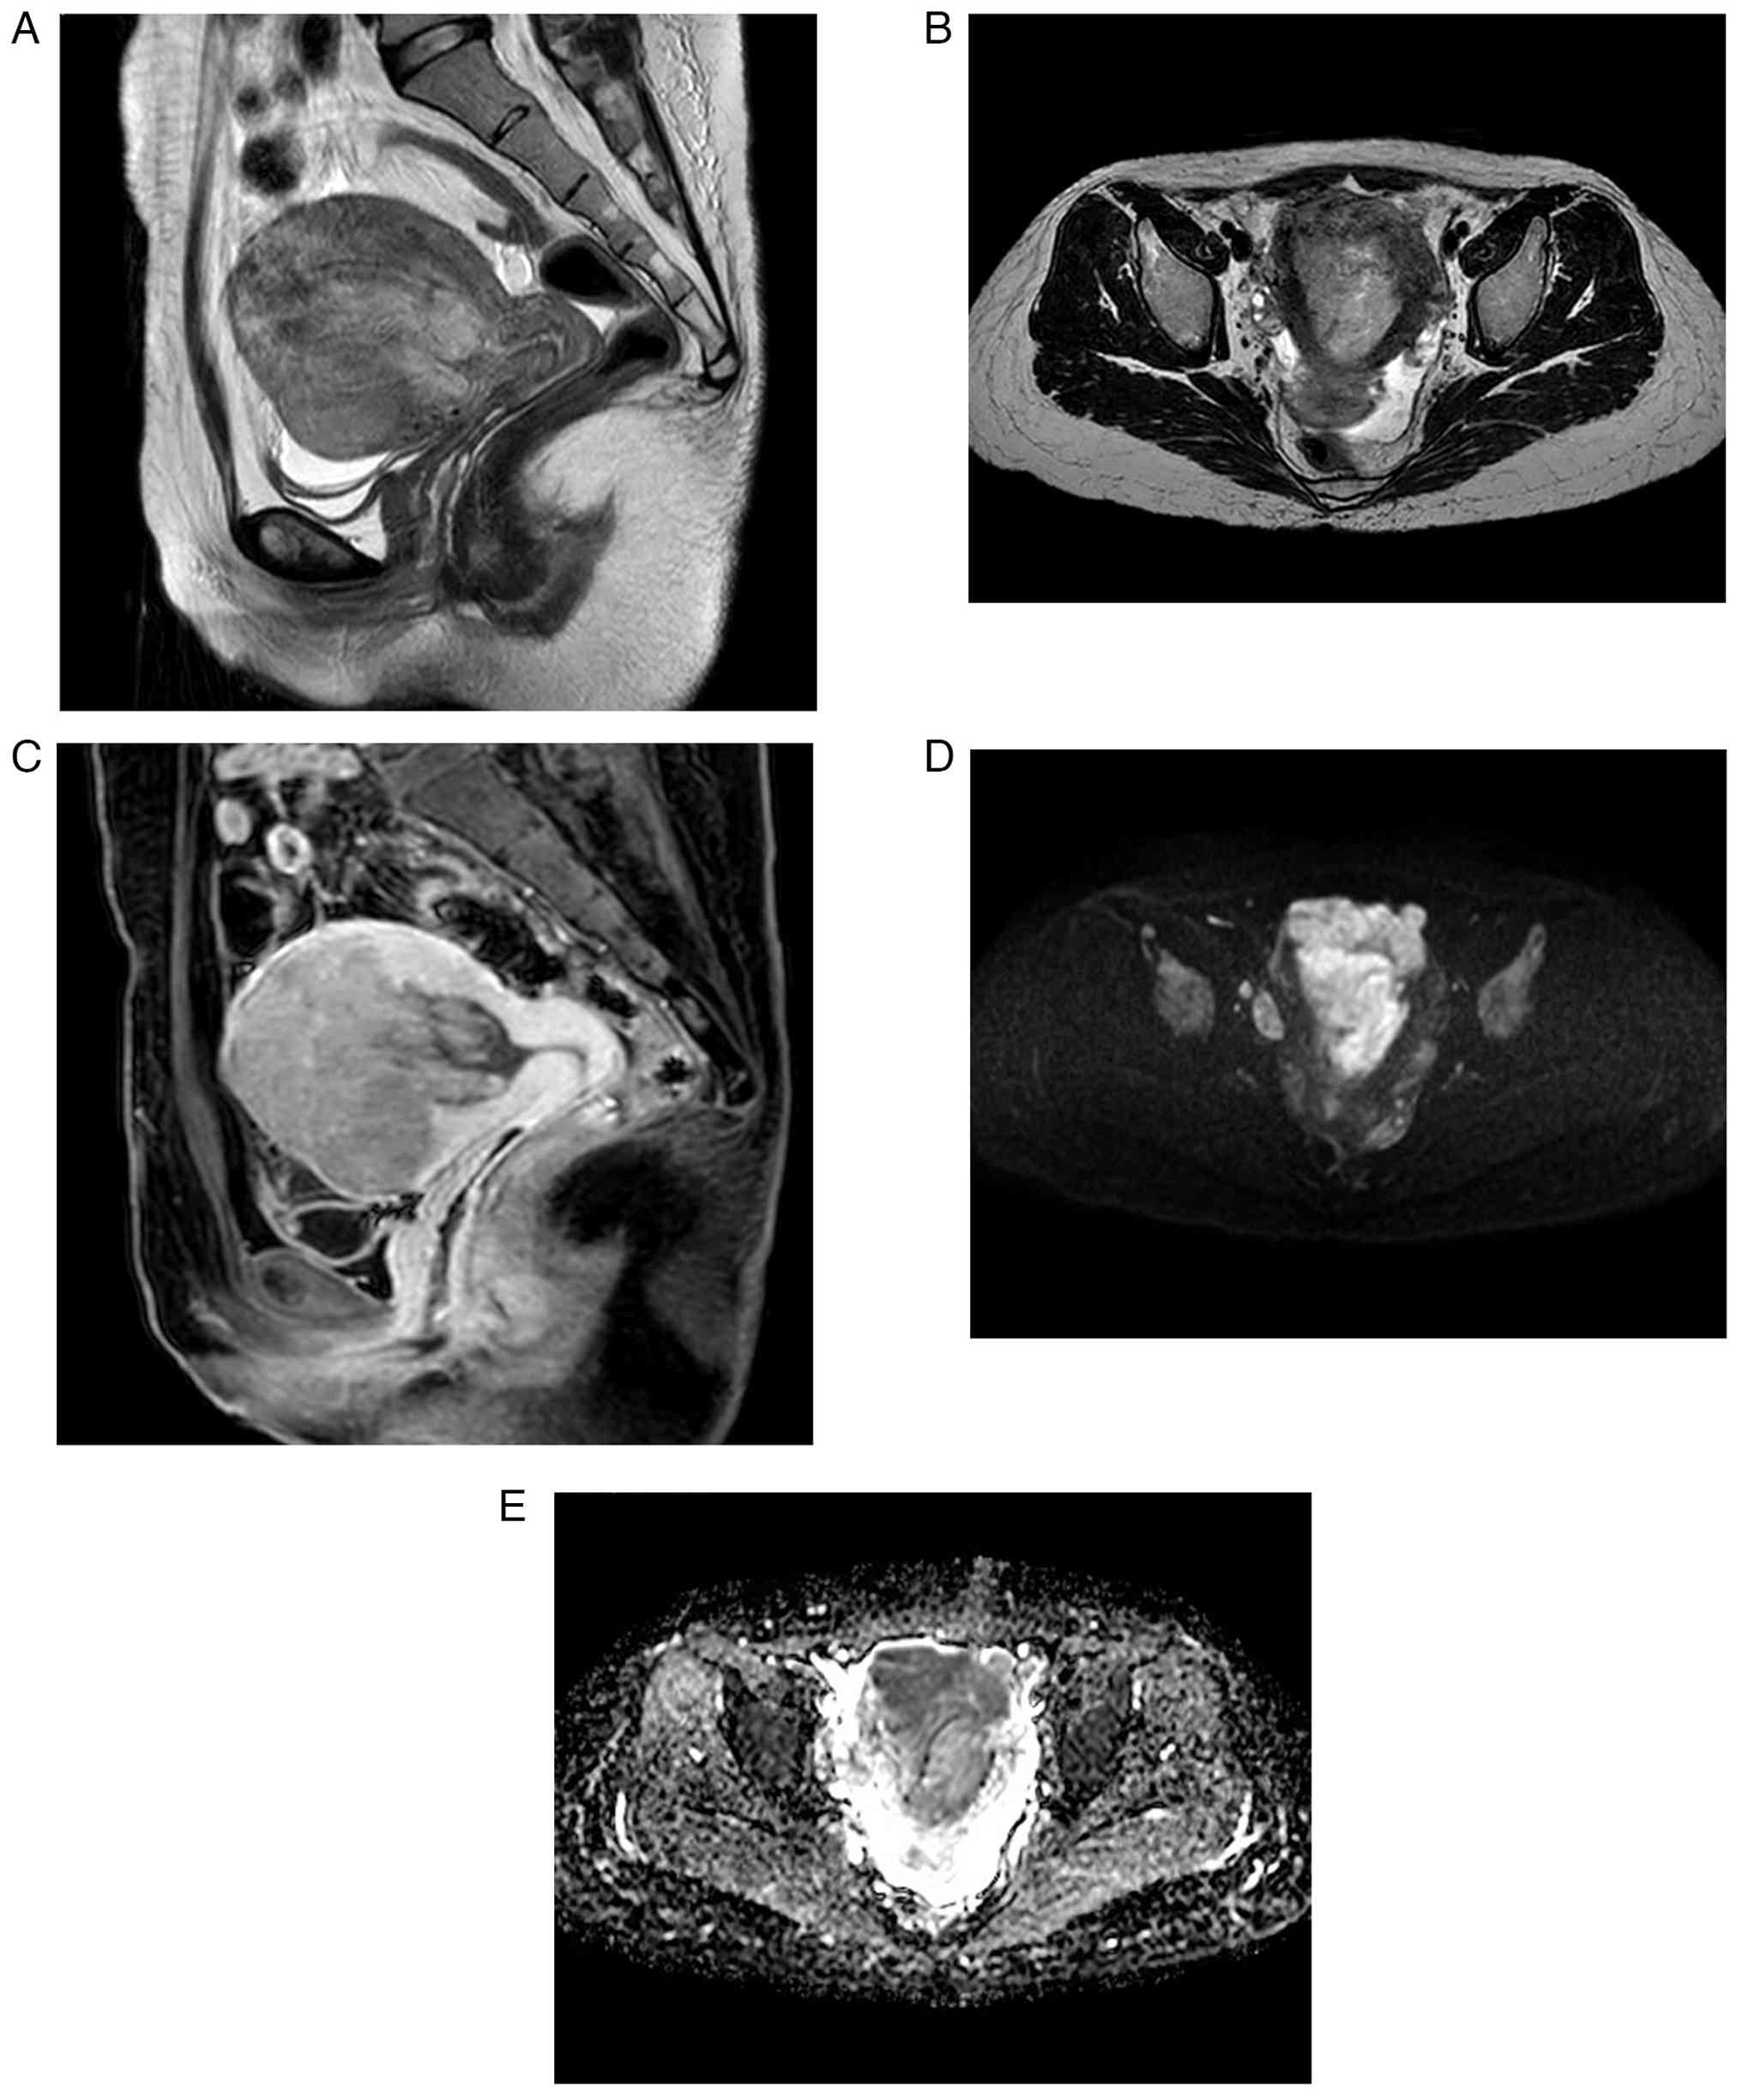

Pelvic magnetic resonance imaging revealed an irregular mass with mild contrast enhancement and restricted diffusion. This protruded from the myometrium into the uterine cavity (Fig. 1A-E). As both cervical and endometrial cytology were negative, a hysteroscopic biopsy of the tumor was performed. The tumor was white, irregular, and showed neovascularization (Fig. 2A). Endometrial biopsy revealed densely proliferating epithelioid cells with nuclear atypia and prominent mitoses, consistent with poorly differentiated carcinoma. However, atypical polygonal cells were also present. Immunohistochemistry showed reduced epithelial marker expression and weak positivity for smooth muscle markers, raising the possibility of carcinosarcoma (Fig. 2B-E). Computed tomography (CT) revealed para-aortic and pelvic lymph node metastasis and multiple pulmonary metastases (Fig. 3A-C). The patient underwent total hysterectomy with bilateral salpingo-oophorectomy to control genital bleeding and obtain a definitive diagnosis.

MRI findings. (A) Sagittal T2-weighted

MRI showing an irregular uterine mass protruding from the

myometrium into the endometrial cavity. (B) Axial T2-weighted MRI

demonstrating the same uterine mass with heterogeneous SI. (C)

Contrast-enhanced MRI showing mild enhancement of the lesion. (D)

Diffusion-weighted imaging demonstrating high SI in the lesion. (E)

Apparent diffusion coefficient map showing corresponding low SI,

indicating diffusion restriction. SI, signal intensity.

MRI findings. (A) Sagittal T2-weighted MRI showing an irregular uterine mass protruding from the myometrium into the endometrial cavity. (B) Axial T2-weighted MRI demonstrating the same uterine mass with heterogeneous SI. (C) Contrast-enhanced MRI showing mild enhancement of the lesion. (D) Diffusion-weighted imaging demonstrating high SI in the lesion. (E) Apparent diffusion coefficient map showing corresponding low SI, indicating diffusion restriction. SI, signal intensity.